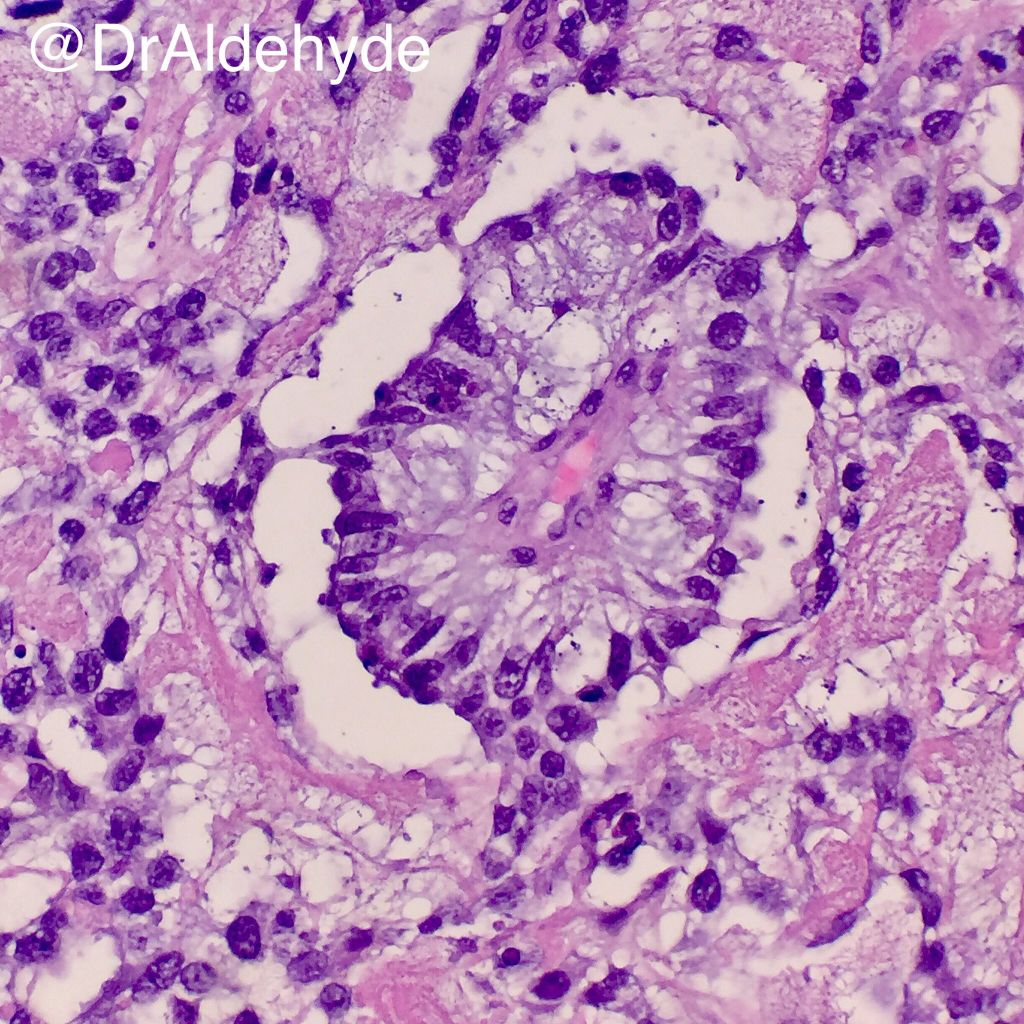

Discover the clinical significance of Schiller-Duval bodies, the pathognomonic histological hallmark of yolk sac tumors. Learn how these distinctive glomeruloid structures aid in the accurate diagnosis of endodermal sinus tumors. Explore the connection between these diagnostic markers, germ cell neoplasia, and elevated alpha-fetoprotein levels in this essential overview for pathology students and medical professionals.

Read full article: Schiller Duval Bodies